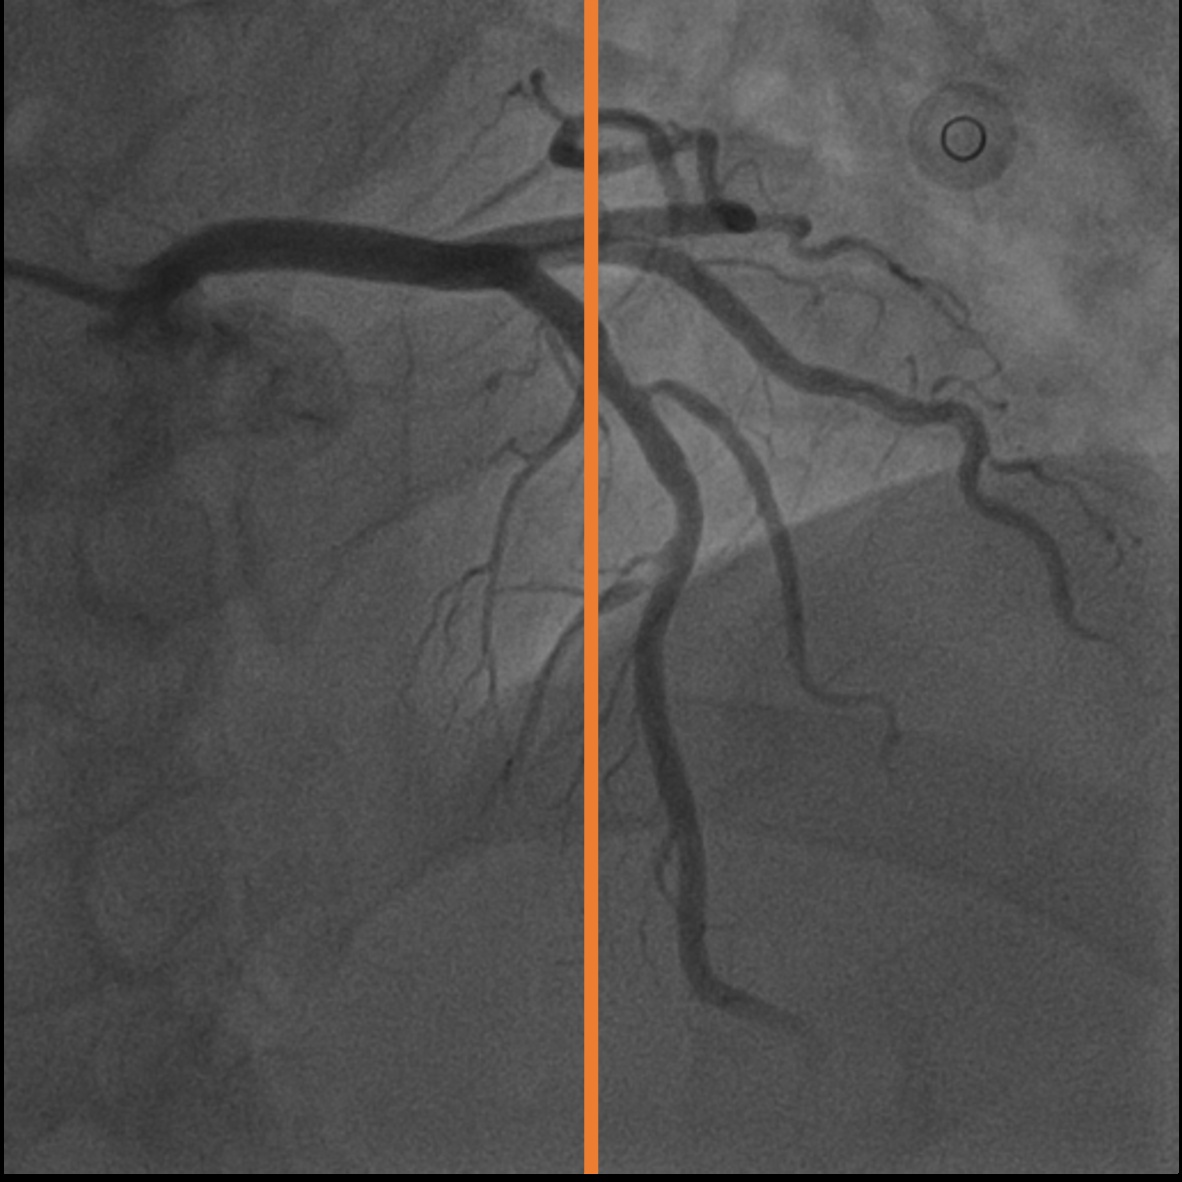

A.2 Temporal Coherency

Our method takes an entire X-ray video as input, thus producing segmentation results with better temporal coherency. Temporal coherency is essential for making medical diagnoses, especially when dealing with blood flow in vessels. Therefore, we conduct visual comparisons between our method and other compared methods by slicing horizontally or vertically and stacking the segmentation results. The results in Figure 11 show our method strikes a better balance between segmentation accuracy and temporal coherency. While other baseline methods either produce false segmentation results or do not maintain consistent prediction along the temporal dimension.